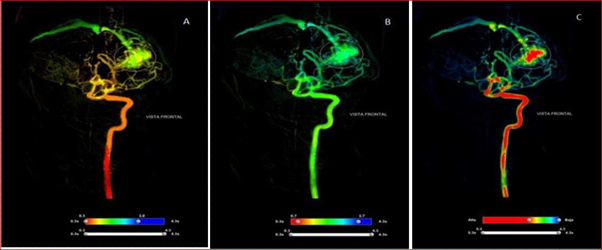

A 26-year-old female patient, Karnofsky index4 90 points. She abruptly presented intense headache, vomiting, and photophobia. In the initial brain computed tomography (CT scan), haemorrhage is objective in the left cerebellar hemisphere, entering the Intensive Care Unit. At 24 hours, it presents degradation of the state of consciousness due to obstructive triventricular hydrocephaly. It is decided to place peritoneal ventricular derivative system with medium-pressure opening valve and evidence of neurological event resolution. Within 15 days of the onset of symptoms in the study of Angio CT scan, arteriovenous malformation (AVM) is diagnosed in the left cerebellar hemisphere, DSA (Figure 1 A, B and C) and two-dimensional tissue perfusion are performed (Figures 2 & 3).

Figure 2 Tissular perfusion by two-dimensional angiography of arteriovenous malformation in the left cerebellar hemisphere. Front view with a parametric flow scale.

Parameters: A, arrival time; B, time to peak contrast; C, absorption index and D, area under the curve

We use standard brain angiography methods with percutaneous access by modified Seldinger technique, to the right femoral artery by retrograde puncture. Spinal catheter 5 Fr was used for selective intubation of each vertebral artery. After positioning the angiographic catheter, contrast was injected (10 ml Iopamidol 370, Unique Pharmaceutical) at a range of 5 mL/sec. with a programming of 3 images/sec. with Mark 7 Arterion automatic injector pump. The record is continued until the opacification of the major cerebral venous sinus is visualised. The time density curves are automatically calculated from DSA images with parametric colour encoding that allows the extraction of post-procedure data (Figures 2 & 3).

Two dimensional (2D) perfusion brain angiography made it possible to visualize apparent blood flow, blood volume, and average transit time. Observing a high-flow AVM in the left cerebellar hemisphere, small (maximum diameter 28.23mm), given by its rapid filling (0.7 seconds) and the visualization of early venous drainage in the early arterial phase, recruiting a considerable volume of blood taking into account the distribution of the iodized contrast used according to the parametric flow scale, with greater uptake and permanence of the contrast in the torch of the lesion, which lasts throughout the arterial phase (3.7 seconds), appreciating even in the late venous phase.